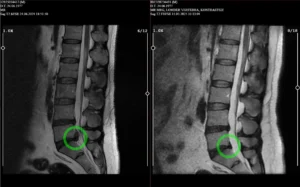

Ameliyatsız Bel Fıtığı Tedavisi

Cerrahi müdahaleye gerek kalmadan bel fıtığına etkili ve güvenli çözümler sunuyoruz

Nükleoplasti Tedavisi

Eklem ağrılarınızı hafifleten, hareket özgürlüğünüzü geri kazandıran tedaviler